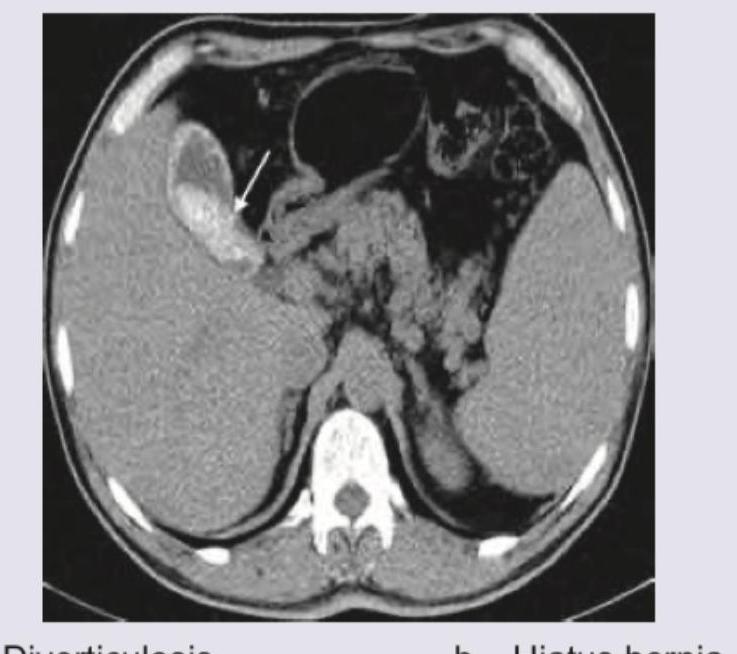

CT abdomen shows: (Recent NEET Pattern 2016-17)

Explanation: ***Diverticulosis*** - The image shows an out-pouching of the colonic wall (indicated by the white arrow), characteristic of a **diverticulum**. - **Diverticulosis** refers to the presence of multiple such diverticula, often seen in the colon on CT scans. *Hiatus hernia* - A hiatus hernia involves the protrusion of the **stomach** through the **esophageal hiatus** of the diaphragm into the chest cavity. - This image does not show any gastric organ extending above the diaphragm. *Gallstones* - Gallstones are calcified deposits found within the **gallbladder**, appearing as bright, high-density structures. - The structure indicated by the arrow is clearly an out-pouching of the bowel wall, not a calcified stone within the gallbladder. *Acute pancreatitis* - Acute pancreatitis is characterized by **inflammation of the pancreas**, often visible as pancreatic enlargement, peripancreatic fat stranding, and fluid collections. - The image does not show any signs suggestive of pancreatic inflammation or changes in the pancreas itself.